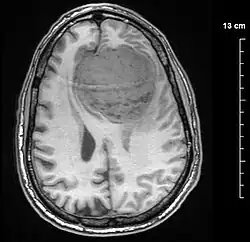

An MRI of the brain, demonstrating the appearance of a meningioma

Meningiomas are visualized readily with contrast CT, MRI with gadolinium,[23] and arteriography, all attributed to the fact that meningiomas are extra-axial and vascularized. CSF protein levels are usually found to be elevated when lumbar puncture is used to obtain spinal fluid. On T1-weighted contrast-enhanced MRI, they may show a typical dural tail sign absent in some rare forms of meningiomas.[18]